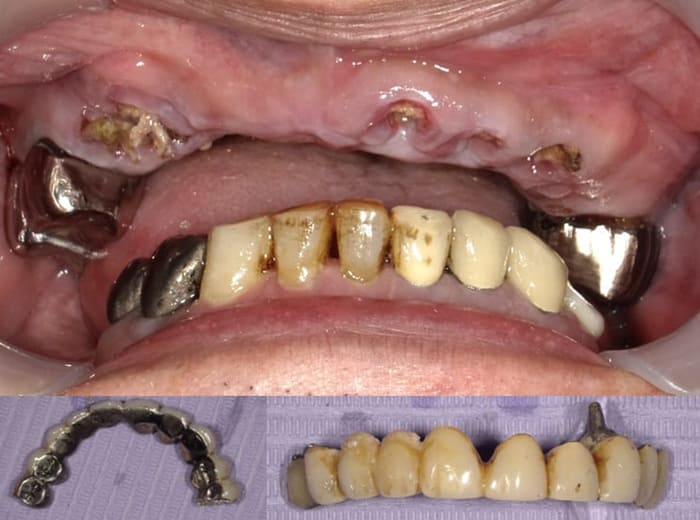

20年ほど前に入れた第2小臼歯から反対側の第2小臼歯まで8本の歯をつないでいたブリッジが取れて噛めなくなり全顎的な治療を希望して来院

上顎前歯を含む第2小臼歯から対側の第2小臼歯までの10本のブリッジが脱離しそれを支えていた歯自体が保存できない状態であった。また下顎の臼歯部も欠損しており、このことで垂直的な咬合の安定が得られず前歯に負担がかかる崩壊脱離したと考えられる。

#15,14,21,22,23,27,36が残根状態で温存は不可能であり、患者さん自身もそれを自覚しておられた。

治療計画と患者さんへの説明

- 上顎の前歯を含めた第2小臼歯までの10本のブリッジが脱離して土台の歯が温存できない状態である。

- 右側上顎臼歯部は下顎の臼歯がないことから、挺出しており左側臼歯部においても咬合平面(歯がかみ合う面の基準)が左右の臼歯部で歪んでいる。

- 上顎の治療が優先されるが温存できる歯は温存して温存できない歯に関しては抜歯し下顎にもインプラント補綴を行い、咬合関係を整えていきましょうとお話し。